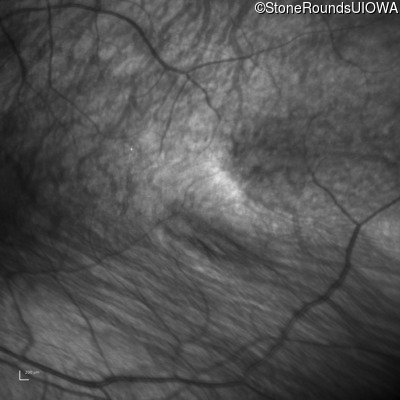

Infrared Fundus Photograph - Right - 10/300 sc

Exemplar